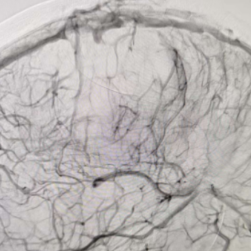

手术当天,医院神经外科专科主任贺礼进、病区主任黄春林带领团队,联合南华附一帮扶专家肖涛,三人配合默契、精准操作,成功将患者颅内大静脉内的血栓完整取出。术后复查结果显示,原本完全堵死的血管全程恢复通畅,血流也恢复正常。